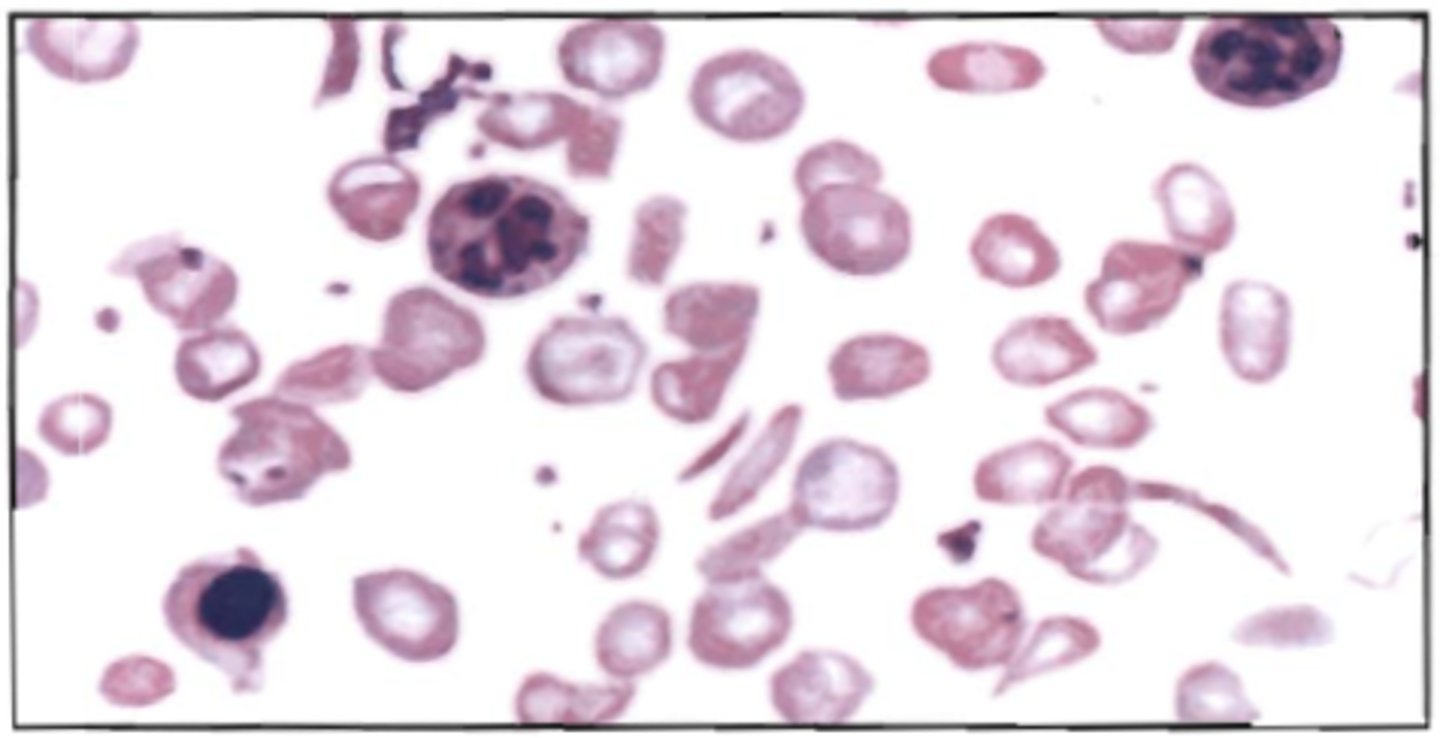

7. Refer to the following illustration:

D. D

88. With this blood picture, an additional test indicated is:

See BOC pg 159

A. alkali denaturation

B. alkaline phosphatase stain

C. peroxidase stain

D. hemoglobin electrophoresis

<p>88. With this blood picture, an additional test indicated is:</p><p>See BOC pg 159</p><p>A. alkali denaturation</p><p>B. alkaline phosphatase stain</p><p>C. peroxidase stain</p><p>D. hemoglobin electrophoresis</p>